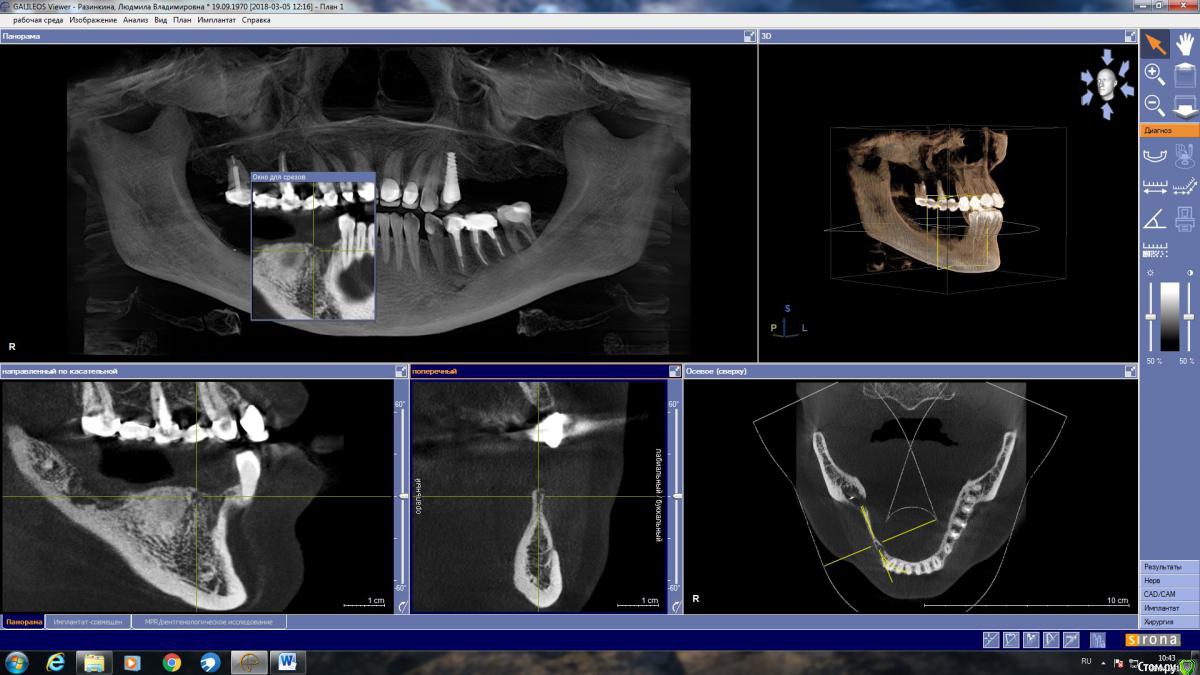

LjudmilaRaz Опубликовано 27 апреля, 2018 Поделиться Опубликовано 27 апреля, 2018 Здравствуйте! Напишите, пожалуйста, своё мнение. В первую очередь планирую имплантацию снизу справа!Обращалась на консультацию к трем врачам. Первый имплантолог предложил нарастить кость и установить четыре импланта. Врач работает только с имплантами одной фирмы (немецкие). Смутило, что полгода назад вариант был совершенно другой и еще то, что очень дорого.Второй предлагает нарастить кость и установить имплант Астра на месте удаленной в декабре четверки со смещением ближе к месту пятерки, и имплант Анкилоз на месте семерки со смещением к шестерке. То есть, накрыв мостом, получится не четыре, а три зуба.Такой же вариант, но с южно-корейскими имплантами (работаю только с ними), предложил третий имплантолог. Это относится к случаю, когда если двое говорят разное, то стоит послушать третьего ? Ссылка на комментарий

LjudmilaRaz Опубликовано 10 мая, 2018 Автор Поделиться Опубликовано 10 мая, 2018 Здравствуйте!С врачом определилась, опытный ЧЛХ стоматолог-имплантолог, еще раз сходила на консультацию. Он считает, что в моем случае более щадяще будет использование костной пластины животного происхождения, которая, становясь после определенных манипуляций пластичной, обогнет с обеих сторон в районе 4 и 5 снизу справа, где в дальнейшем планируется установка двух имплантов (плюс еще один в районе 7-ки - в итоге 3 штуки). По его мнению, ранее им планируемое расщепление в моём случае может стать по факту невозможным, из-за анатомически неблагоприятной ситуации - мало кости. Есть место (практически 2 мм) где при рассечении кость может "съесться" инструментом.Только в моей голове всё сложилось, и тут новый виток. Что думаете про такой способ костной пластики для моего случая. Ссылка на комментарий